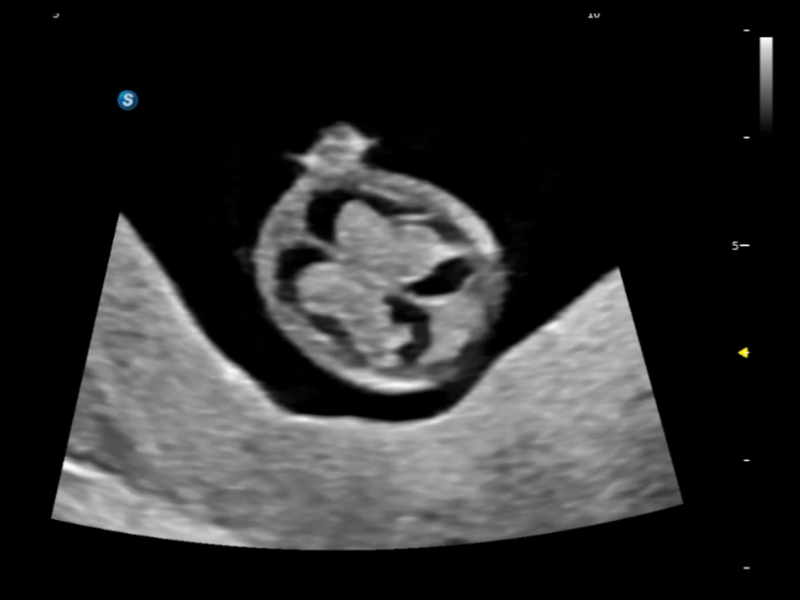

丰富的血流动力学检测技术,可在不同医疗场景中高效捕捉血流信号,助力临床诊疗。

在传统血流的基础上优化扫查和算法策略,能够更好的抑制组织信息,提炼红细胞运动信息,得到更高帧频,高灵敏度和分辨率的血流信号,还原更真实的血流动力学。

通过光照模型,使二维血流显示出立体的效果,增加血流的敏感性、成束性,减少外溢。可以和其他不同的血流技术联合使用,融合不同技术的优势。轻松应对微小血管,增强血流的立体效果,提升视觉敏感性。

通过创新的Matrix E自适应滤波算法,能有效滤除软组织和噪声信号,最大限度保留超低速微细血流的信号;结合超长时间域算法,极大提升细微血流的敏感性和空间分辨率,更真实的反应组织、包块的血流灌注情况。